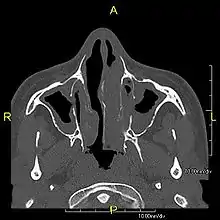

Around 80% of people with primary ciliary dyskinesia experience respiratory problems beginning within a day of birth. Many have a collapsed lobe of the lung and blood oxygen low enough to require treatment with supplemental oxygen.[3] Within the first few months of life, most develop a chronic mucus-producing cough and runny nose.[3] The main consequence of impaired ciliary function is reduced or absent mucus clearance from the lungs, and susceptibility to chronic recurrent respiratory infections, including sinusitis, bronchitis, pneumonia, and otitis media. Progressive damage to the respiratory system is common, including progressive bronchiectasis beginning in early childhood, and sinus disease (sometimes becoming severe in adults). However, diagnosis is often missed early in life despite the characteristic signs and symptoms.[4] In males, immotility of sperm can lead to infertility, although conception remains possible through the use of in vitro fertilization, there also are reported cases where sperm were able to move.[5] Trials have also shown that there is a marked reduction in fertility in females with Kartagener's syndrome due to dysfunction of the oviductal cilia.[6]

Many affected individuals experience hearing loss and show symptoms of otitis media which demonstrates variable responsiveness to the insertion of myringotomy tubes or grommets. Some patients have a poor sense of smell, which is believed to accompany high mucus production in the sinuses (although others report normal – or even acute – sensitivity to smell and taste). Clinical progression of the disease is variable, with lung transplantation required in severe cases. Susceptibility to infections can be drastically reduced by an early diagnosis. Treatment with various chest physiotherapy techniques has been observed to reduce the incidence of lung infection and to slow the progression of bronchiectasis dramatically. Aggressive treatment of sinus disease beginning at an early age is believed to slow long-term sinus damage (although this has not yet been adequately documented). Aggressive measures to enhance clearance of mucus, prevent respiratory infections, and treat bacterial superinfections have been observed to slow lung-disease progression. The predicted incidence is 1 in approximately 7500.[7]

Several diagnostic tests for this condition have been proposed.[16] These include nasal nitric oxide levels as a screening test, light microscopy of biopsies for ciliary beat pattern and frequency and electron microscopic examination of dynein arms, as the definite diagnosis method. Genetic testing has also been proposed but this is difficult given that there are multiple genes involved.